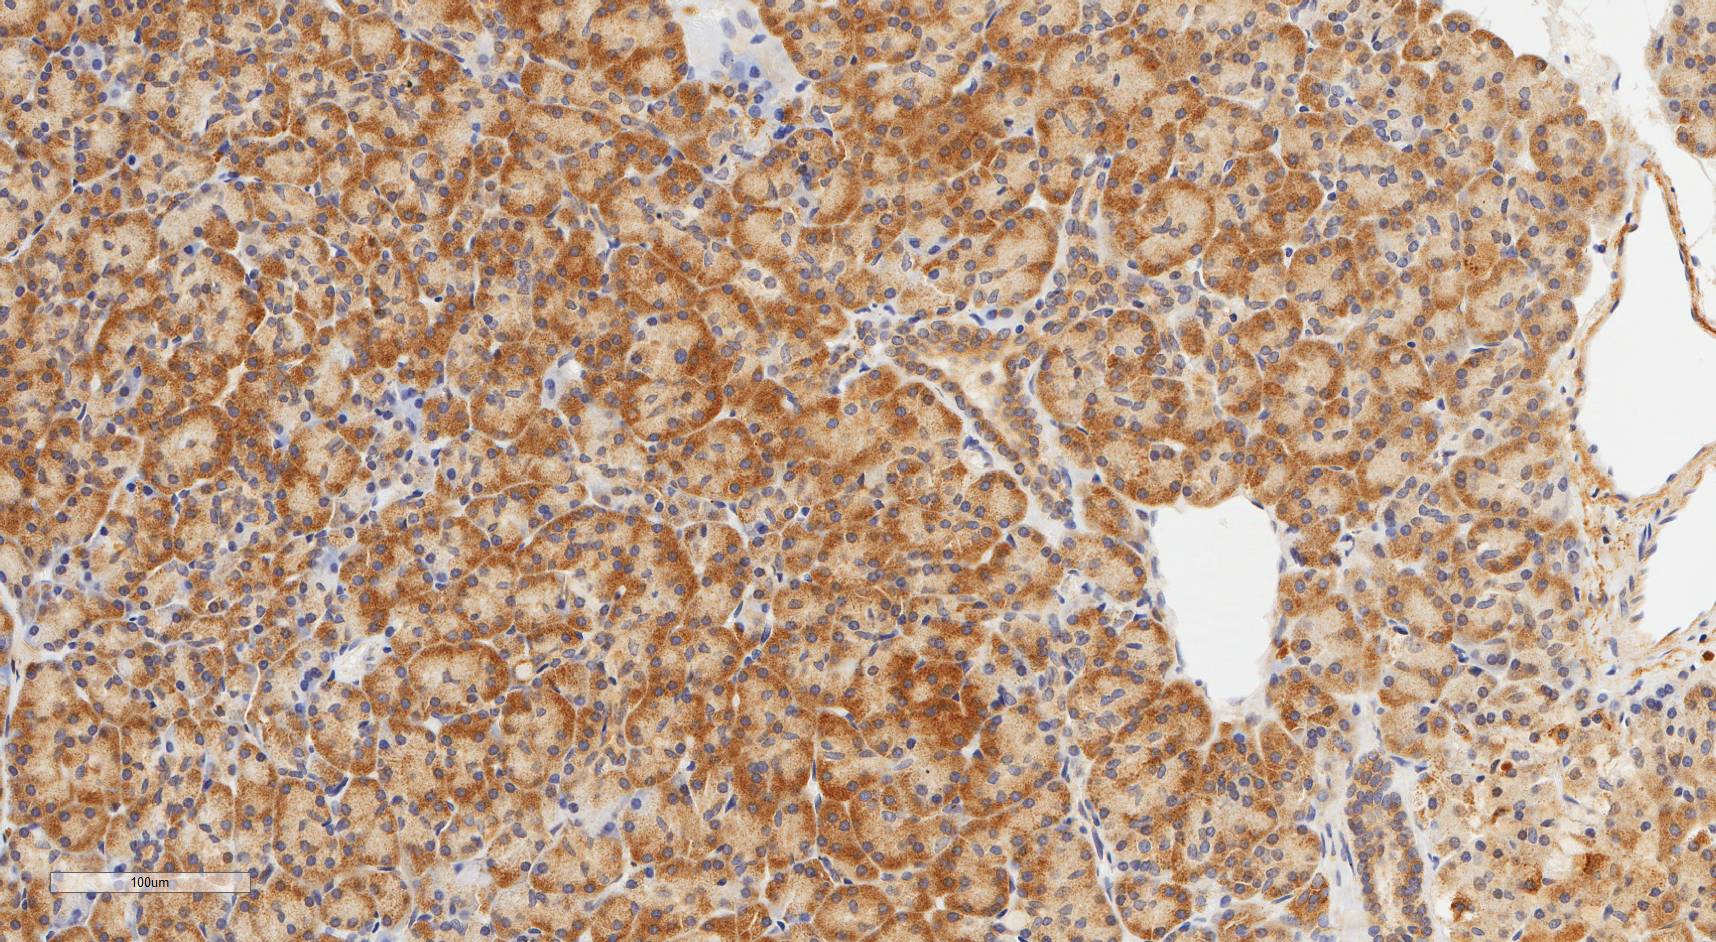

Laminin N terminus alpha31 (LaNt a31) is a really interesting laminin-related protein that the Hamill lab has been investigating for a while. Until recently, our studies focused entirely on the epithelial tissues of the skin, the surface of the eye and oral squamous cell carcinoma. However, we’ve always known that this relatively unstudied protein is also expressed by other tissues. As a first (and really important) step to understanding what this protein’s role is in tissue function, we used our new mouse monoclonal antibodies against the human form of LaNt a31 to screen a wide-range of human tissues.

Below you can see some of our favourite images from the selection. Click on an image to view as a slideshow.

You can see the whole story in the paper by Lee Troughton et al., available here.